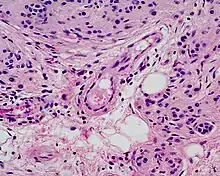

Benign congenital nevi can have histological characteristics resembling melanomas, often breaking most if not all of the ABCDE rules. Dermatoscopic findings of the smaller forms of benign congenital nevi can aid in their differentiation from other pigmented neoplasms.[5]

Microscopically, congenital melanocytic nevi appear similar to acquired nevi with two notable exceptions. For the congenital nevus, the neval cells are found deeper into the dermis. Also, the deeper nevus cells can be found along with neurovascular bundles, with both surrounding hair follicles, sebaceous glands, and subcutaneous fat. Such annexes and the Subcutaneous tissue can also be hypoplasic or, conversely, present aspects of hamartoma.